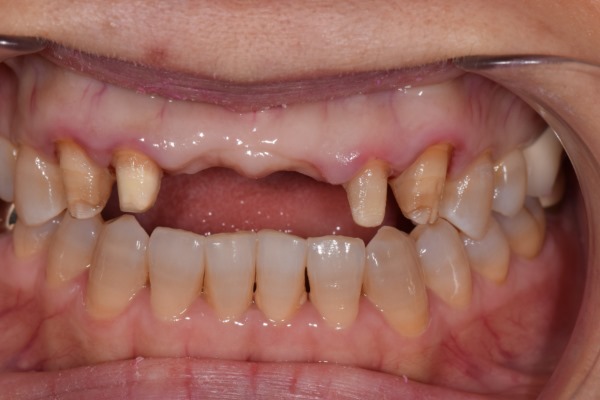

윗니 치아 3번부터 - 3번까지 6개 치아를 브릿지(연결되어 있는 크라운)로 예전에 치료 경험 있는 환자분이 오셨어요. 위 환자분께서는 안쪽엔 금속(메탈)을 포함하고 겉면은 치아색인 PFM 크라운을 사용 중이셨어요.

앞니에 이러한 PFM을 사용 시 치아와 잇몸라인 쪽에 지금처럼 검은 선이 생기게 되죠. 또한 치아 색도 원래의 자가치아보다 색감이 어둡게 나올 수밖에 없습니다. (자가 치아의 색은 약간의 투명감을 띄고 있죠)

환자분은 기존 앞니에 많은 불만을 갖고 계셨어요.

일단 기존의 크라운을 제거한 후 잇몸라인을 정리해야 할 것 같죠? 잇몸성형을 함께 진행 한 후

새로운 크라운의 색을 결정해야 합니다. 치아색은 새로 하는 6개 치아만은 생각해선 안되겠죠. 주변 치아와의 색의 조합, 크기,모양의 조합도 생각해야 합니다.